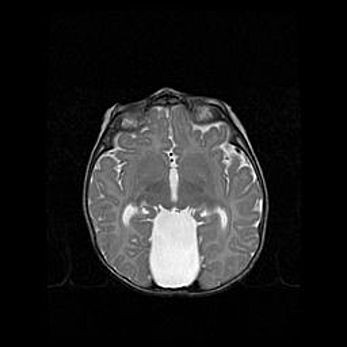

Мальформация Денди-Уокера. Киста задней черепной ямки.

Агенезия мозолистого тела.

Возраст: 2,5 месяца

Вес: 2420 г

Пол: женский

Окружность головы: 37 см

Срок гестации: 32 недели

Мальформация Денди—Уокера — редкий вид патологии ЦНС, представляющий собой врожденный порок развития каудального отдела ствола и червя мозжечка, ведущий к неполному раскрытию срединной (Мажанди) и латеральных (Лушка) апертур IV желудочка мозга. Для этогно синдрома характерна триада симптомов: гипотрофия червя мозжечка и/или полушарий мозжечка, кисты задней черепной ямки, гидроцефалия различной степени. В 70% случаев порок сочетается и с другими аномалиями головного мозга, в частности с агенезией мозолистого тела.